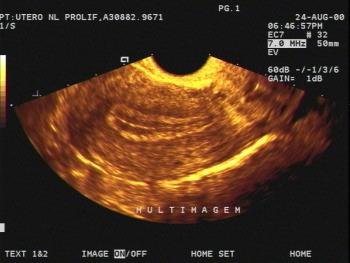

Three-dimensional ultrasound (3D US) is a new imaging modality, which is being introduced into clinical practice. Although this technique will not probably replace two-dimensional ultrasound, it is being increasingly used.